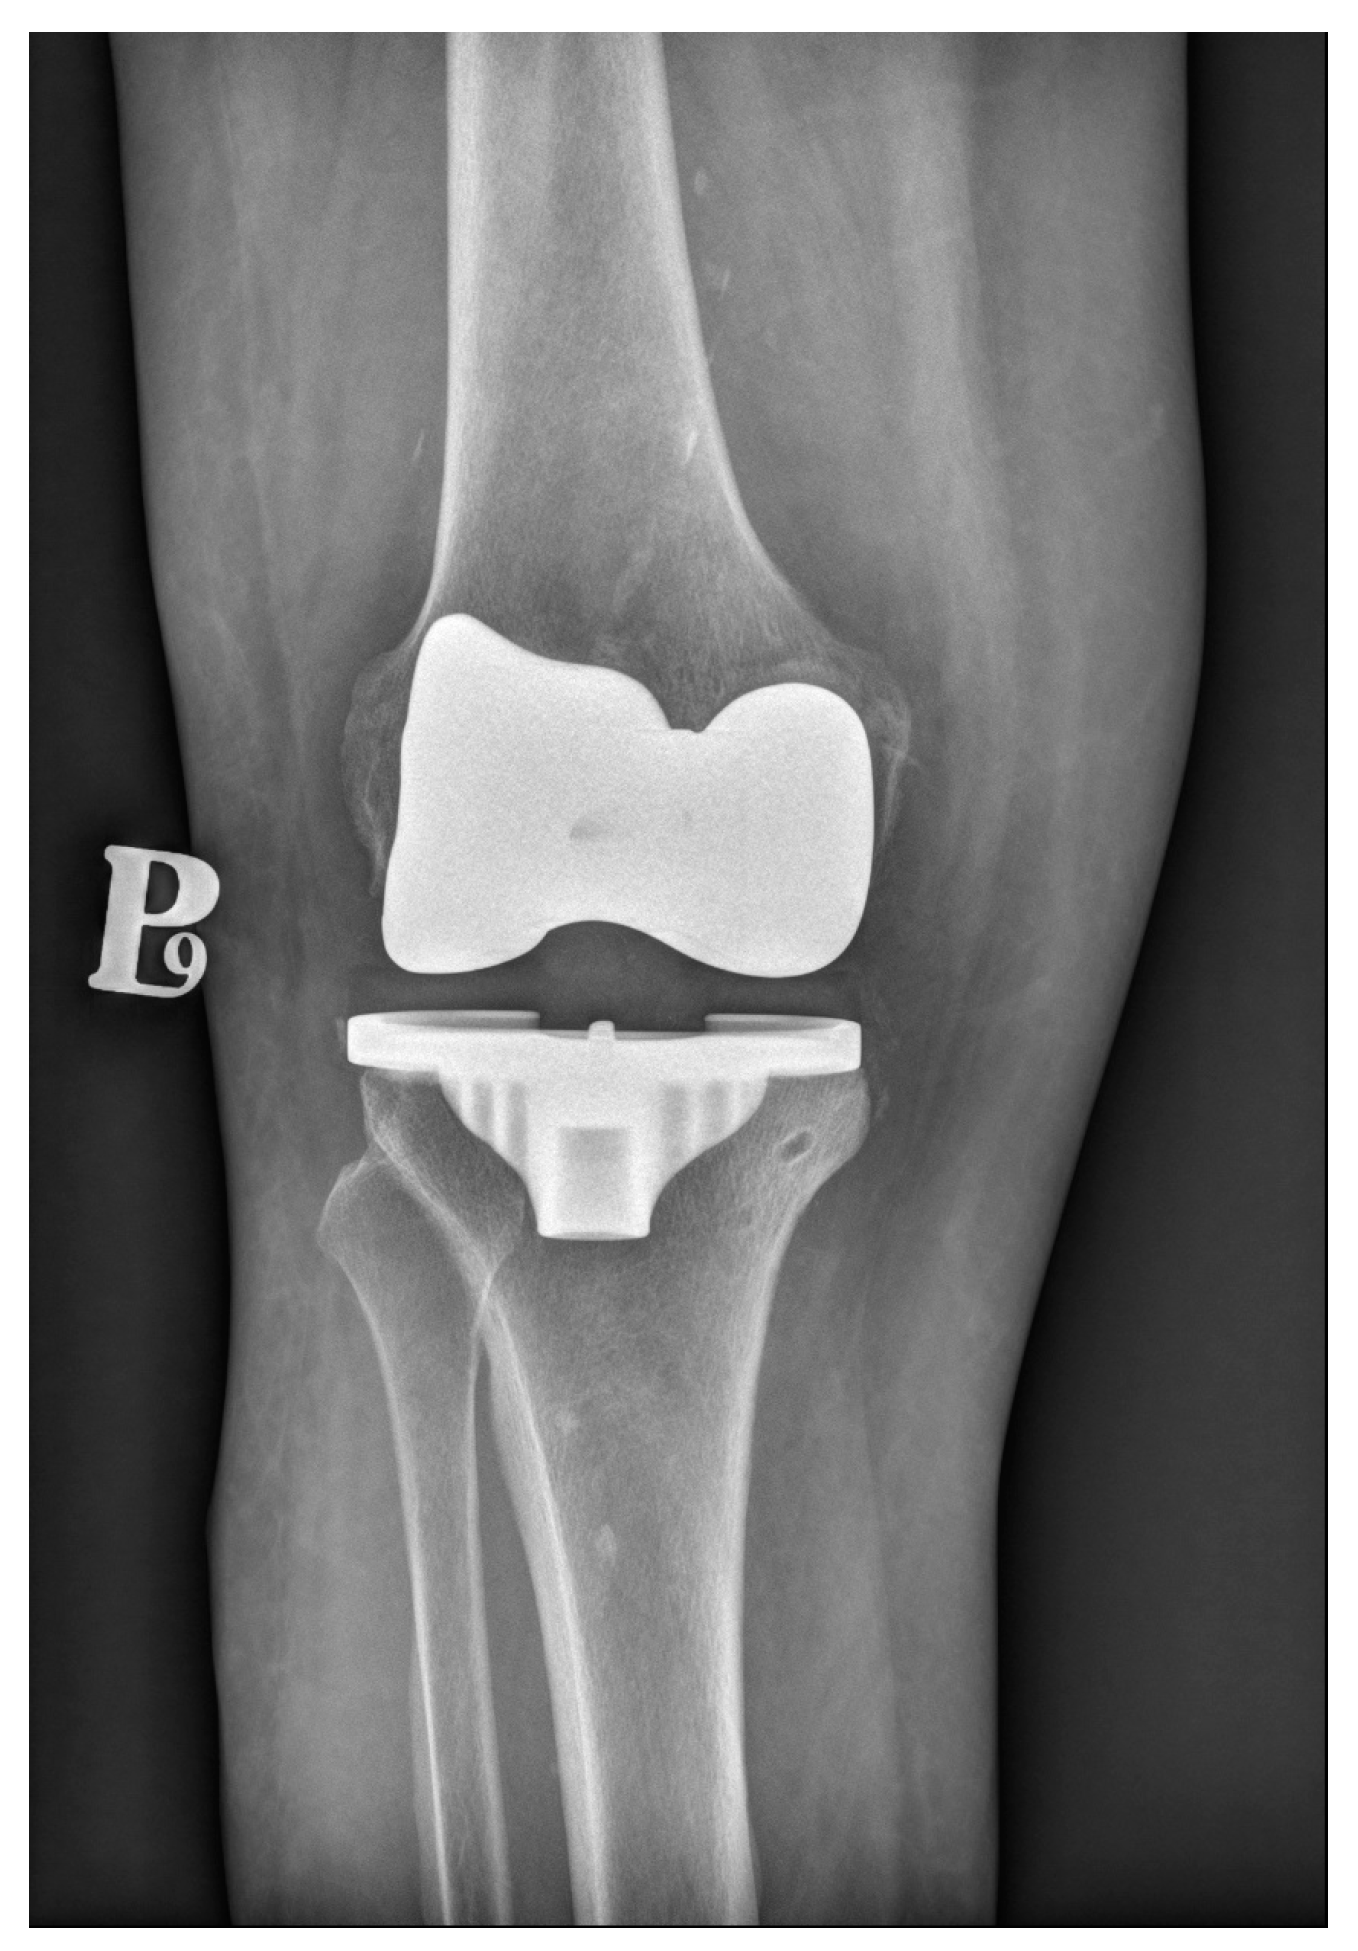

Knee arthroplasty is one of the most commonly performed orthopedic procedures. There are two main types of fixation methods—cemented (which is shown in Figure 2) and cementless. A third type available is hybrid fixation, which is not very common. In the hybrid fixation, the tibial side is cemented, and the femoral side is cementless. This type of arthroplasty has gained some support from national registries. For example, in the Australian registry from 2022, hybrid TKRs accounted for about 18% of all TKRs, and their 10-year survivorship was superior to full-cemented or cementless TKRs [54]. The cemented type has been the gold-standard since the beginning of performing arthroplasties until today. In reference to the registries included in our review, 77.6% of all primary TKAs in the USA in 2022 were cemented [55].

Figure 2.

Conventional radiograph presenting cemented total knee replacement.